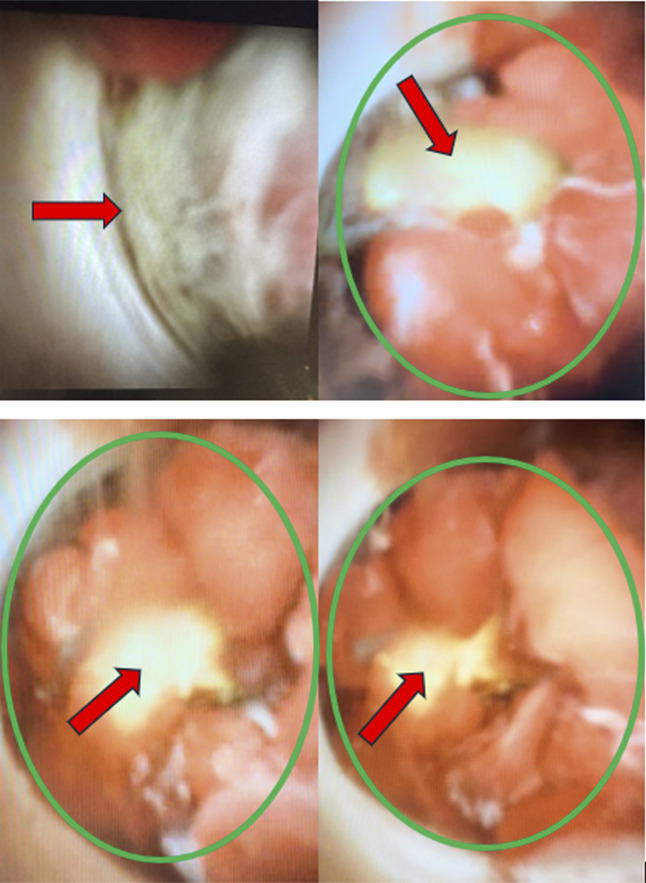

胆管癌是一种罕见的胃肠道恶性肿瘤,年发病率为每10万人0.3 - 6例,通常约95%的病例报告为腺癌。它可以是遗传易感性和各种危险因素共同作用的结果,如但不限于胆总管囊肿、胆石症/胆总管结石,但由于难以获得诊断组织,其诊断具有挑战性。在这项研究中,我们提出了一个具有挑战性的诊断病例,揭示了胆管门周区域未分化的破骨细胞样巨细胞癌。

Cholangiocarcinoma is a rare gastrointestinal malignancy with an annual incidence of 0.3 to 6 cases per 100,000, and, usually, it is reported as adenocarcinoma in about 95% of the cases. It can develop as a result of combination of genetic predispositions and various risk factors like but not limited to choledochal cysts, cholelithiasis/choledocholithiasis, yet its diagnosis is challenging due to difficulties in obtaining tissue for diagnosis. In this study, we present a challenging case in diagnosis that reveals undifferentiated carcinoma with osteoclast-like giant cells in the perihilar region of the bile duct.